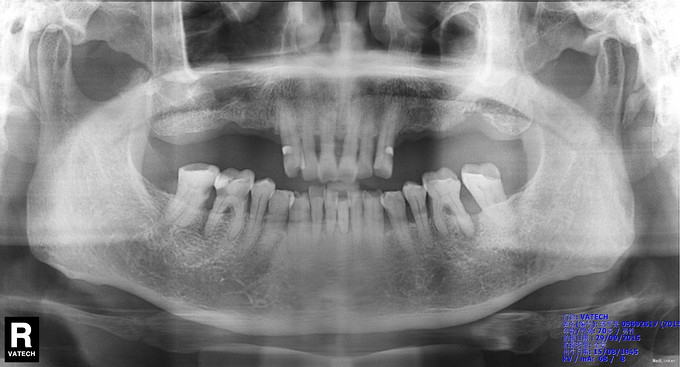

检查:36颊侧颈部楔形缺损,探敏感,远中邻面深牙周袋,探诊深度约5mm,可探及龈下牙石,舌侧可探入根分叉区约1-2mm,叩痛不适,无明显松动,牙龈红肿 X线示:36牙槽骨吸收至根中1/3,远中根尖及根分叉区见低密度影像

诊断:36牙周-牙髓联合病变 治疗计划:1、36牙周基础治疗 2、36根管治疗 治疗:1. 36碧兰麻局麻下牙合面开髓,暴露髓腔,降牙合,探及MB、ML、DB、DL四个根管口,MB、ML根管内大量血性渗出,DB、DL根管内少量脓性渗出,3%过氧化氢和0.9%生理盐水冲洗,隔湿,干燥,MB、ML根管口置非砷慢失活剂,DB、DL根管口置CP棉球,氧化锌水门汀暂封。 36龈下刮治,根面平整,3%过氧化氢和0.9%生理盐水冲洗,上碘甘油,嘱勿用患牙咬物。 2.主诉:左下后牙上次治疗后疼痛缓解 检查:36暂封物在,叩痛(—),牙体无松动,牙龈无明显红肿。 处置:36去除暂封物,拔残髓,10号C锉疏通根管,干燥根管,电测工作长度均为20mm。EDTA下,常规预备至35#,3%过氧化氢和0.9%生理盐水冲洗+超声荡洗根管交替进行。隔湿,干燥根管,封CP棉球, 氧化锌水门汀暂封。嘱勿用患牙咬物。 3.主诉:左下后牙上次治疗后无不适。 检查:36暂封物在,叩痛(—),牙体无松动,牙龈无明显红肿。 处置:36去除暂封物,取出棉球,生理盐水冲洗并干燥根管,复测工作长度同前。进口根充糊剂+牙胶尖冷侧压根管充填,氧化锌水门汀暂封。术后拍片示:36根充恰填。嘱勿用患牙咬物。